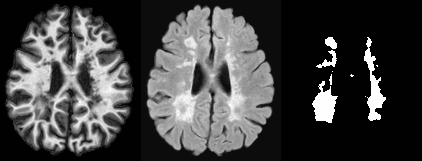

S3DL Sparse Dictionary Learning based MR Image and Lesion Segmentation

Description:Lesion segmentation from T1 and FLAIR